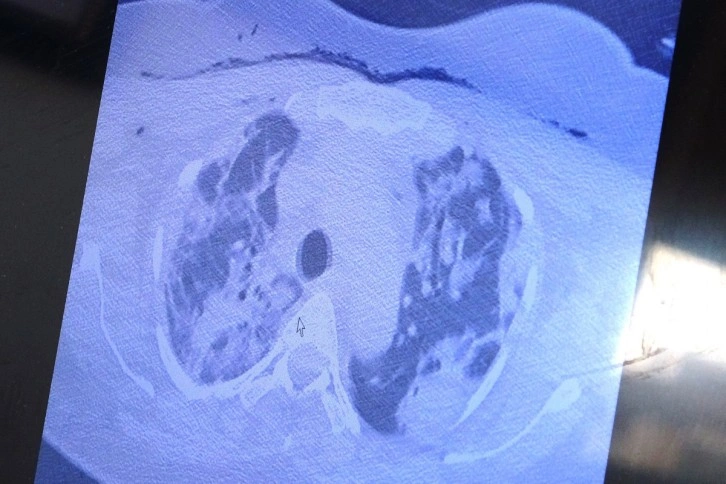

"38 yaşında anne olan kadında ciddi akciğer tutulumları"

Yurt dışından kendisine gelen ve bebeği ile annesini hayata tutunmasını sağlayan Özkaya, "Bu yurt dışında hamileyken kovide yakalan ve ciddi akciğer tutulumu olan 38 yaşında hastamız var. Tedavi olmak için bizim ülkemize geldi. Ciddi solunum yetmezliği vardı. Biz hem annenin hem de bebeğin hayatını garanti altına almak için bebeği aldık. Sağlıkla doğum yaptı. Annenin akciğerine tomografi çektik. Ciddi akciğer tutulumu, ciddi harabiyet olduğunu tomografisinde gördük. Gecen yıllarda gebelerde böyle tutulumlar yoktu" ifadelerini kullandı.